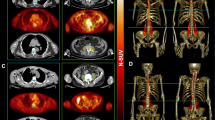

On visual inspection, the radioactivity distribution within the SC was relatively homogeneous without any focal areas of enhanced uptake in both control subjects and ALS patients (Fig. 3a, b). As shown in Fig. 3c–e, the average NSUV was not significantly different between the two groups in the whole spinal canal or in the cervical and dorsal districts. As expected, the average NSUV was significantly lower than the corresponding SC_NSUV in the same districts in both groups (Fig. 3c). By contrast, the radioactivity distribution in the SC showed a different pattern. FDG uptake in the SC was higher in ALS patients than in controls. This difference in FDG uptake between the groups was statistically significant for the whole SC (NSUV 0.82 ± 0.28 in ALS patients vs. 0.70 ± 0.14 in controls, p < 0.05) and for the cervical segment (NSUV 0.99 ± 0.37 vs. 0.85 ± 0.20, respectively; p < 0.05, Fig. 3c, d), but not for the dorsal segment (NSUV 0.72 ± 0.24 vs. 0.62 ± 0.18, respectively; p = 0.08; Fig. 3e).Interestingly, the effect of ALS on FDG accumulation in the SC was independent of demographic and clinical variables. In fact, SC_NSUV did not correlate with age, sex, ALSFRS-R score, time elapsed from diagnosis to PET/CT or riluzole treatment (Fig. 4).

a, b Whole-body maximum intensity projection CT images coregistered with the extracted PET data for the spinal cord in a control subject (a CTR) and an ALS patient (b ALS). The PET data alone are also shown for the corresponding SCs as the average SUV normalized to the corresponding liver values (average NSUV) together with images of the cervical and dorsal segments. c–e Average NSUV for the spinal canal (solid bars) and spinal cord (hatched bars) in control subjects (CTR) and 30 ALS patients (ALS): c whole spinal cord/spinal canal, d cervical segment, e dorsal segment. FDG uptake in the spinal cord was significantly lower in control subjects for the whole spinal cord (c) and for the cervical segment (d), but not for the dorsal segment (e). *p < 0.05